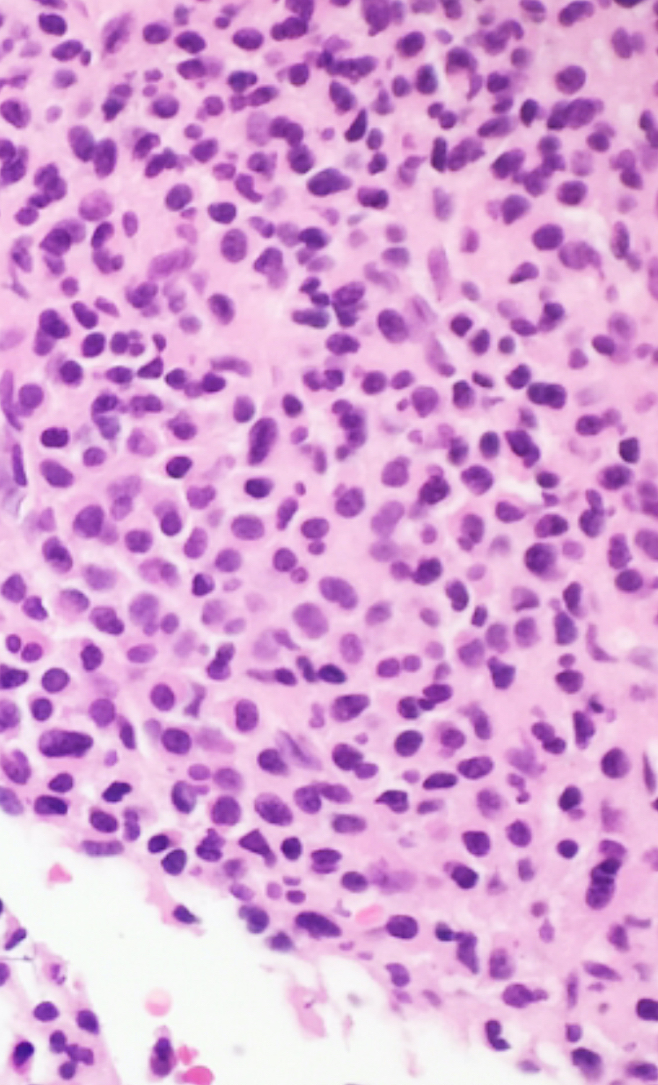

Microscopic (histologic) description

- Core biopsy (Am J Clin Path 1987;87:342):

- Interstitial clusters, nodules or sheets of plasma cells

- Areas of bone marrow may be spared with preserved hematopoiesis, other cases may have diffuse involvement and markedly suppressed hematopoiesis

- Prominent osteoclastic activity may be seen

- IHC to quantify plasma cells (CD138), stains for Ig kappa and lambda to establish clonality

Microscopic (histologic) images

Contributed by Genevieve M. Crane, M.D., Ph.D. and Tapan Bhavsar, M.D., Ph.D.